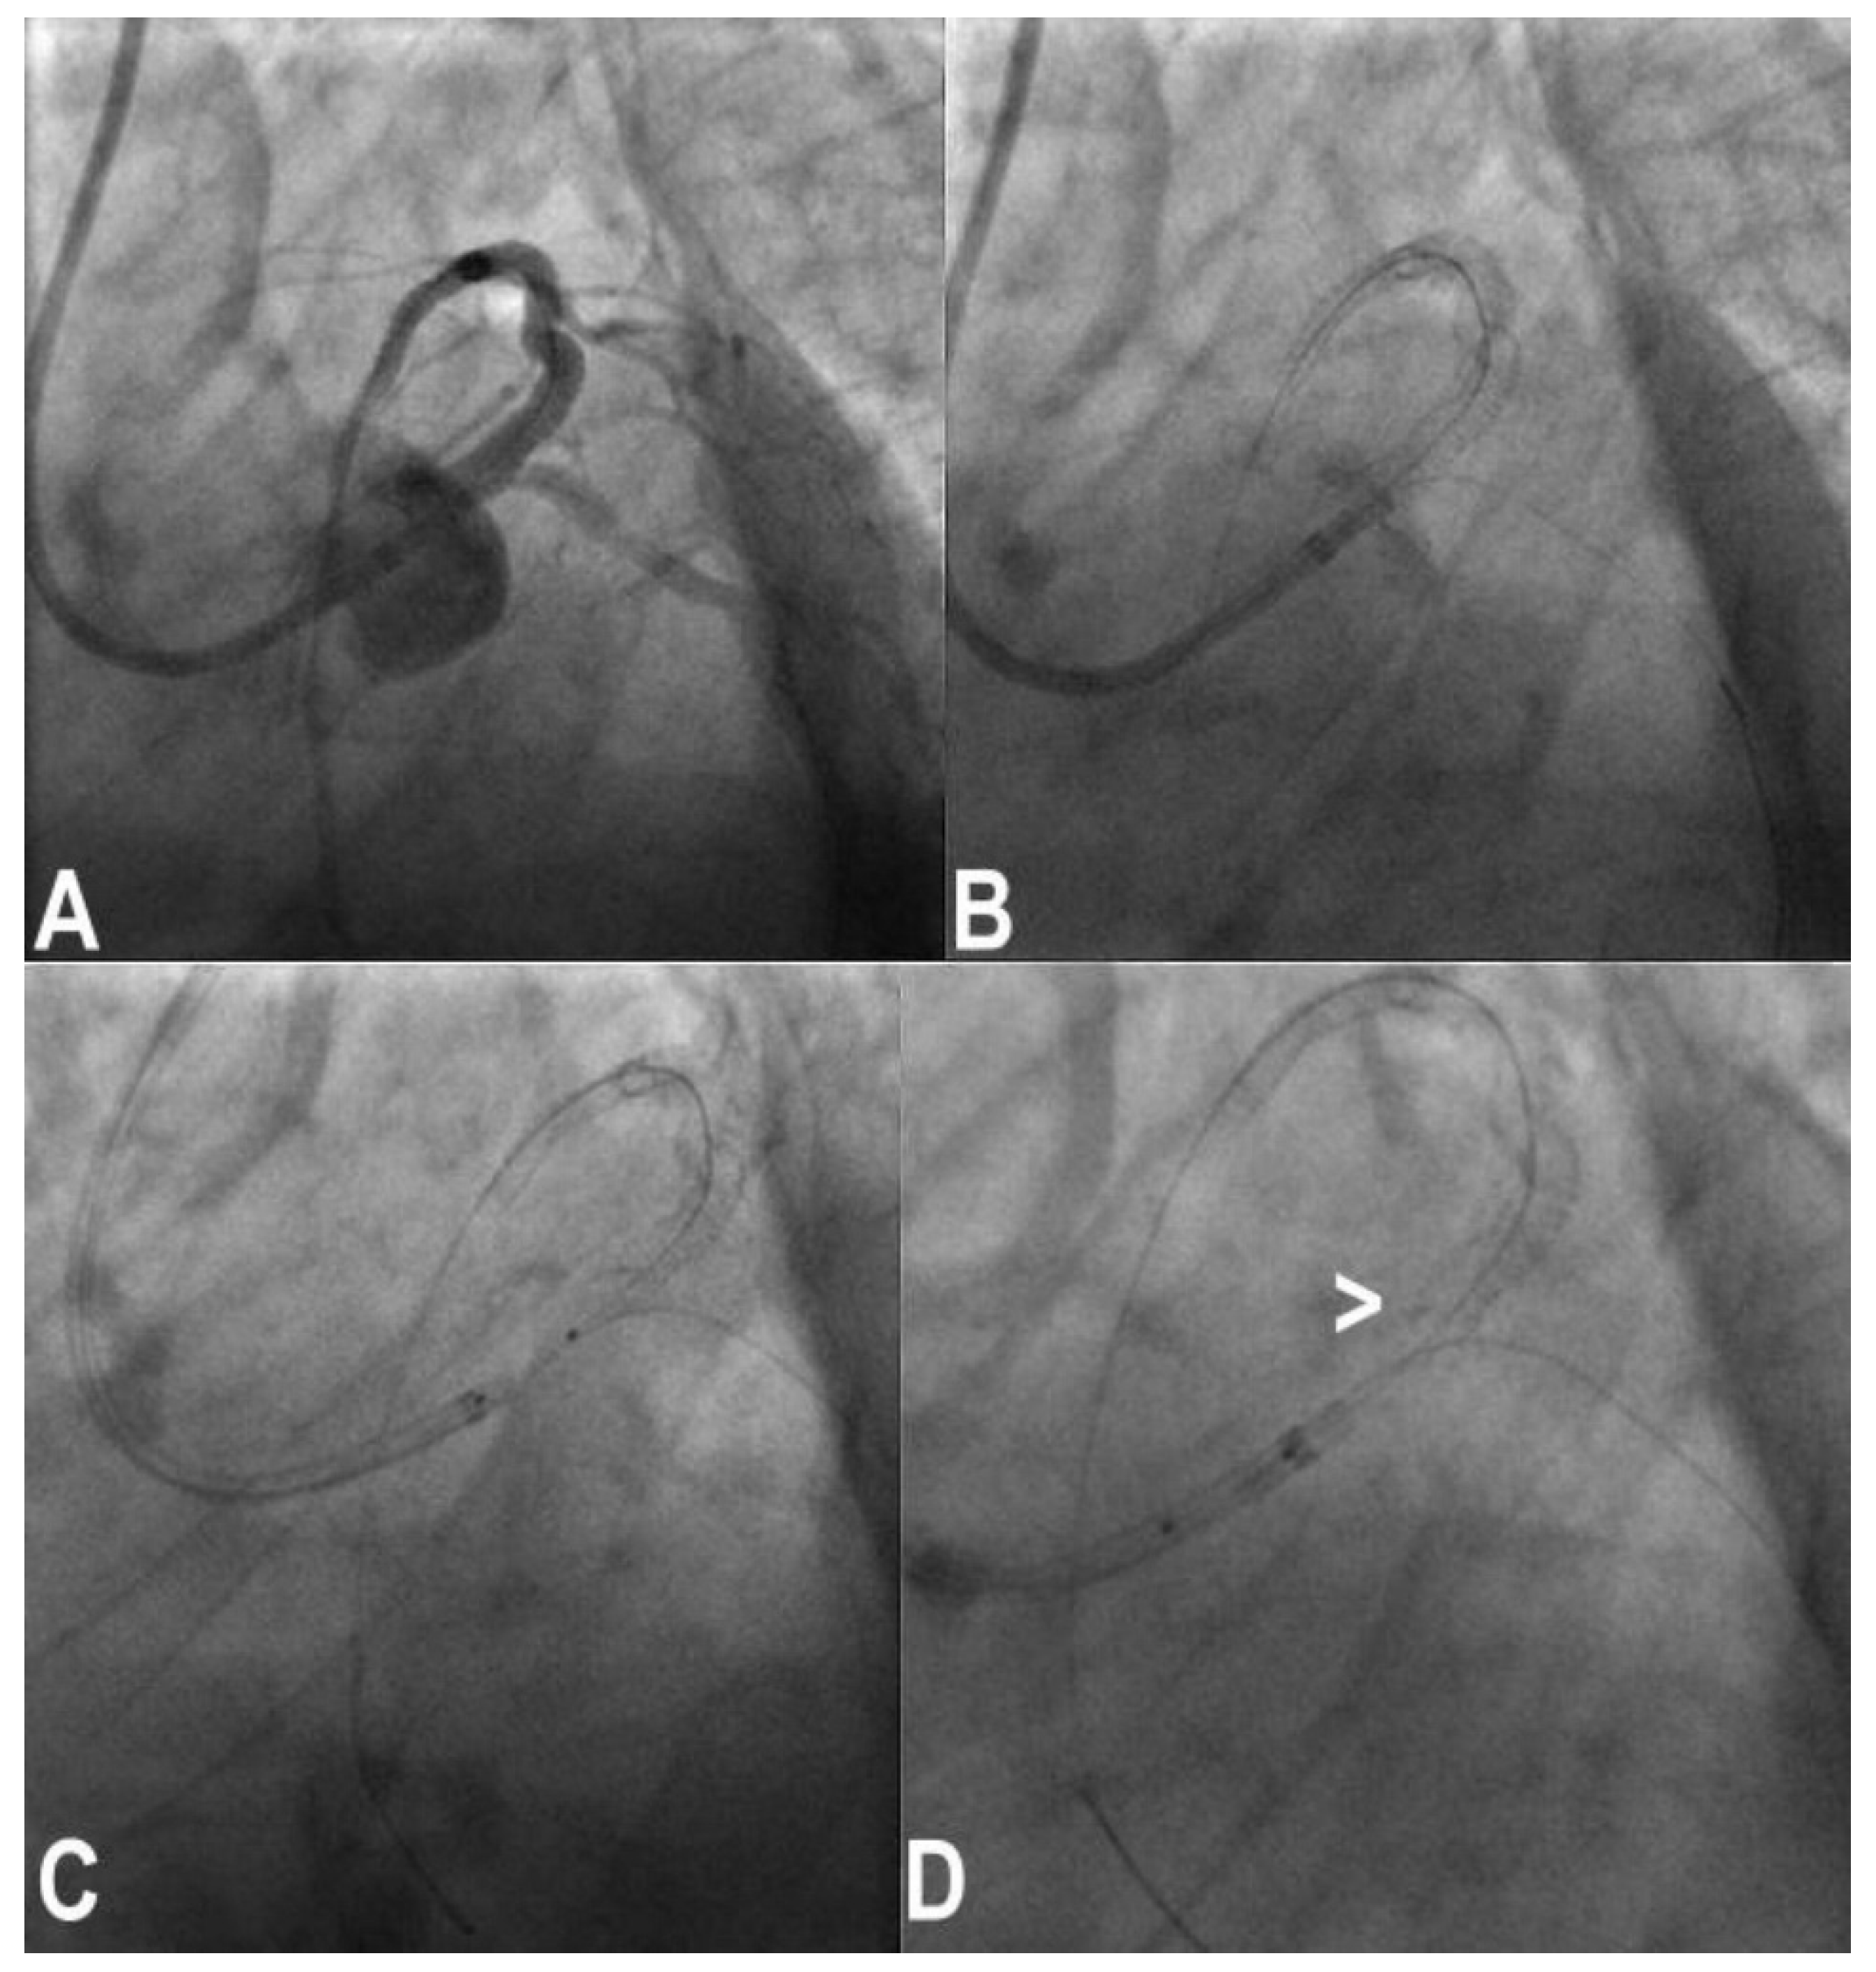

3.7. Wire Entrapment and Fracture